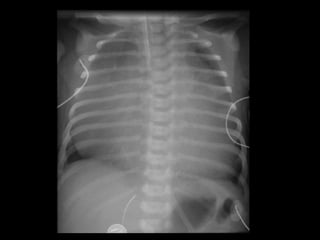

Chest X-ray

What could be the diagnosis

• CXR: prominent RV